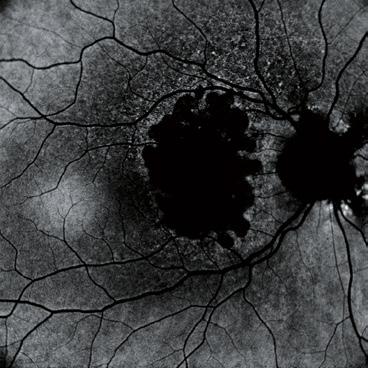

Molecular-scale particles hold promise in new treatments for visual correction. Howard Larkin reports

The multiple lipid, aqueous, mucin and lysozyme-rich layers of the tear film and cornea are highly effective at keeping irritants and pathogens out of the eye. The trouble is, they are nearly as effective at keeping out topical drugs – only 5-to-10% administered typically reach the anterior chamber, David Smadja MD told the 37th Congress of the ESCRS in Paris, France.

Similarly, the sclera blocks topical drugs from the retina and vitreous while the blood-retinal and retinal pigment epithelium barriers restrict systemic drugs. That leaves invasive injections and intravitreal depots as the most effective administration routes for back-of-the-eye treatments, and these are subject to rapid chemical breakdown, added Dr Smadja, who directs and conducts research at Shaare Zedek Medical Centre, Jerusalem, and Bar-Ilan University, Ramat Gan, Israel.

Nanotechnology could change that, Dr Smadja believes. Nanosystems measuring 300nm or less – about three times the diameter of the HIV virus – may overcome problems that reduce drug efficiency by combining and layering even smaller nanoparticles – of 1-to-100nm – with varying chemical, electrical, biologic and physical characteristics. Together, these may be designed to address major challenges in anterior and posterior drug delivery, including drug washout, lack of penetration and enzymatic destruction.

The promise of nanoparticles the ECCTR

Adding positively charged mucoadhesive particles, such as chitosan, to the surface of a nanocapsule could greatly increase residence time in the precorneal space by sticking to the negatively charged posterior layer of tear film (mucine layer), Dr Smadja said. This allows more time for smaller drug particles in the capsule to penetrate the corneal epithelium, reducing washout. Residence time could be further enhanced by placing nanocapsules in a hydrogel matrix or contact lens placed on the ocular surface.

On the corneal surface, nanocapsules could slowly release even smaller capsules coated with lipophilic material designed to move hydrophilic drugs through the lipid-rich epithelium and endothelium. Materials such as hyaluronic acid-chitosan nanoparticles have successfully penetrated cell barriers.

“It’s the old trick we all know, the Trojan horse, where you encapsulate the drug in something that looks friendly,” Dr Smadja said.